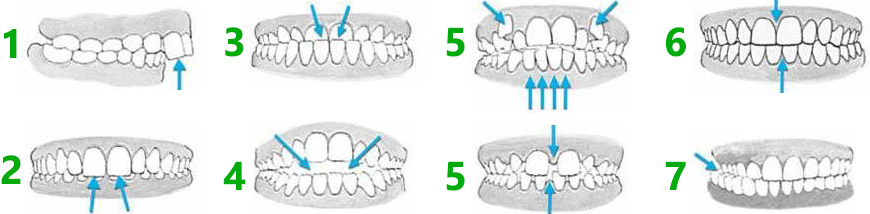

1. آیا دندان های شما حالت جلو آمدگی دارند؟

2. آیا دندان های بالایی سطح زیادی از دندان های پایین را پوشانده است؟

3. آیا دندان های پایین سطح روی دندان های بالا را پوشانده است؟

4. آیا امکان قرار دادن دندان های بالا روی دندان های پایین وجود ندارد؟

5. آیا فضای کافی برای دندان ها در داخل دهان وجود ندارد؟ آیا تعداد دندان های رشد کرده بیش از حد انتظار است؟

6. آیا خطوط لثه ها باهم هماهنگ نیستند؟ زمانی که هماهنگ نباشند، بیمار هنگام خوردن غذا مشکل خواهد داشت.

7. آیا دندان های قدامی فک بالا به جای اینکه روی دندان های پایین قرار بگیرند، داخل این دندان ها قرار گرفته اند؟